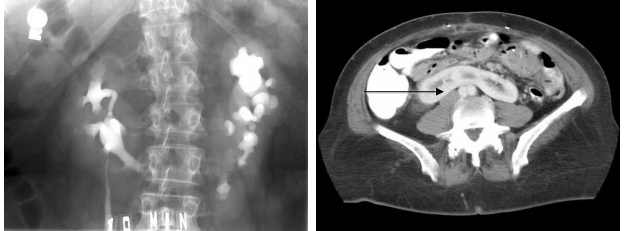

Horseshoe Kidney

Horseshoe Kidney (1/600) is usually asymptomatic and forms when the bilateral metanephric blastema get stuck together in the midline. Because the inferior mesenteric artery comes off of the ventral side of the aorta in the lower abdomen, the now horseshoe-shaped kidney gets caught under this vessel and cannot rise up to its normal location along the dorsal, retroperitoneal wall of the abdomen.

Pelvic Kidney

•One-third of all children born with a pelvic kidney have other complications either with their cardiovascular system, the central nervous system or their urinary system